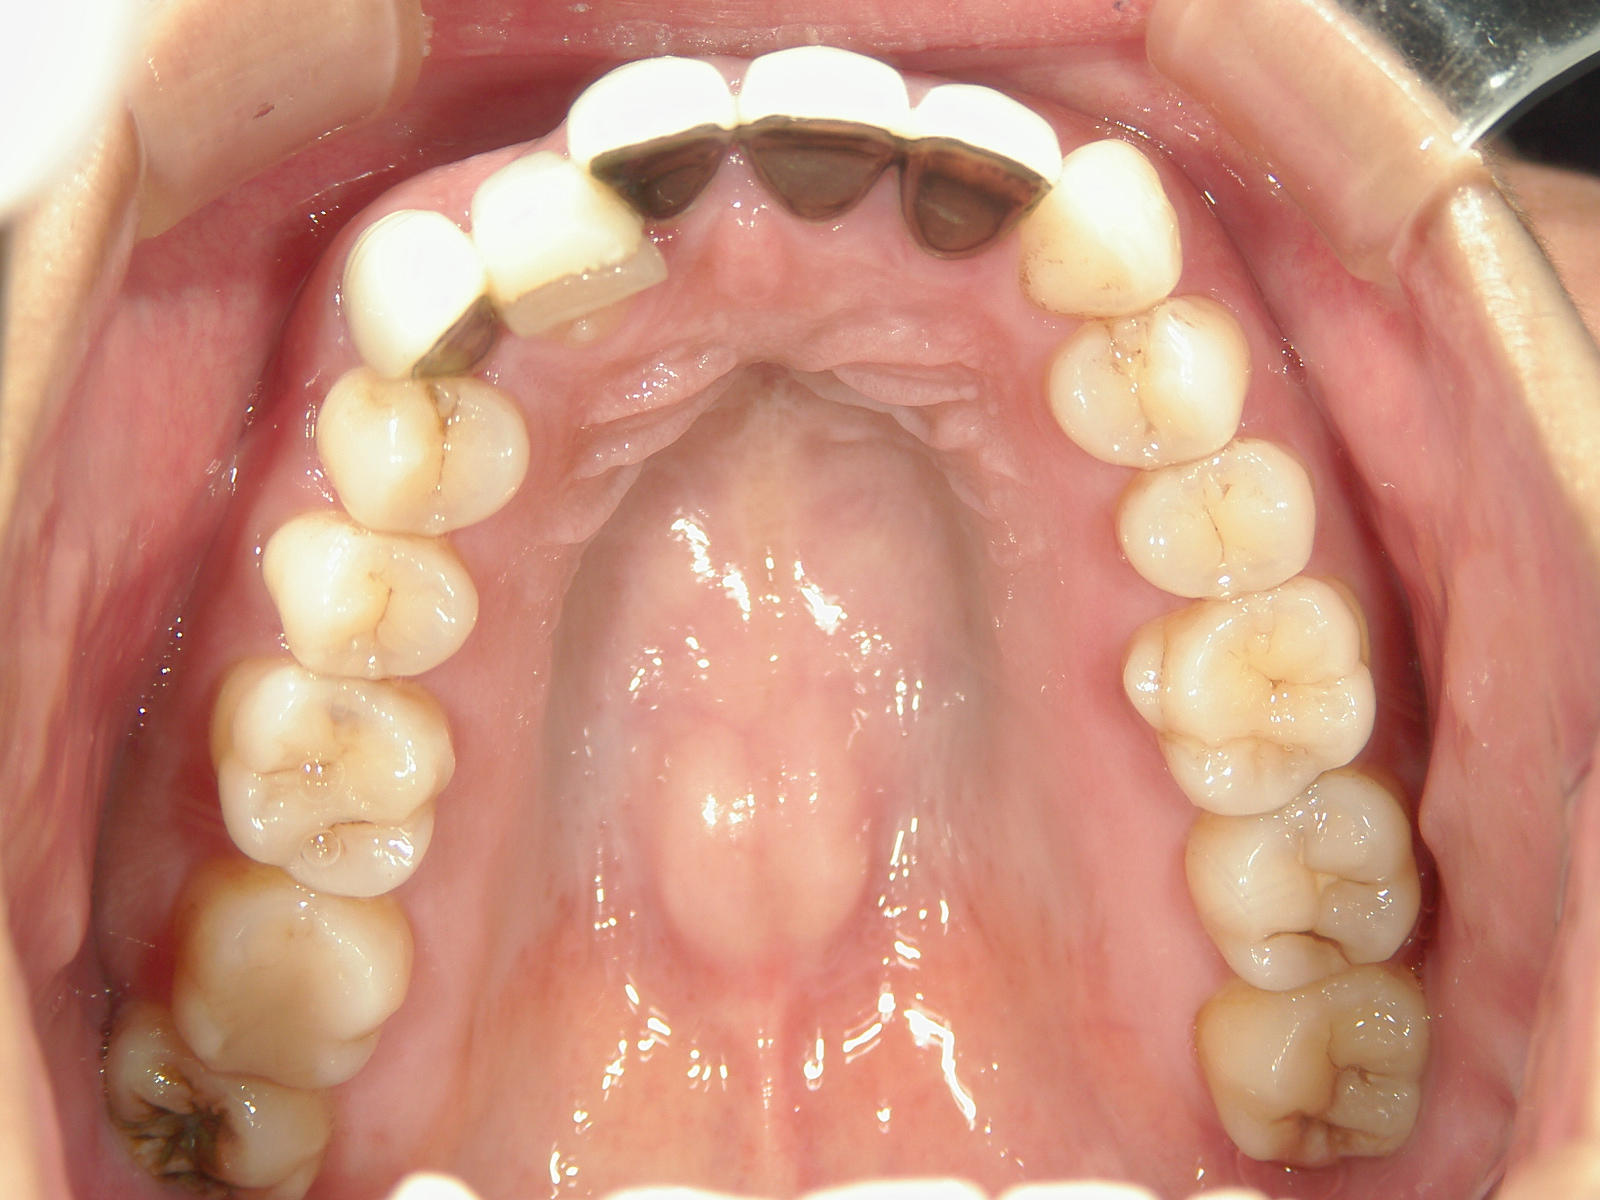

全顎ワイヤー矯正 症例(82)

主訴: 前歯の歯並びが気になる。

上下左右 第一小臼歯(4本)、左右上 親不知(2本)を抜歯。

ミニインプラント、アップライトスプリングを併用。

矯正前に左右上前歯4本を仮歯に変え、矯正治療後にセラミック(SHT)に冠せなおしました。

カテゴリー : ガタガタ(叢生)